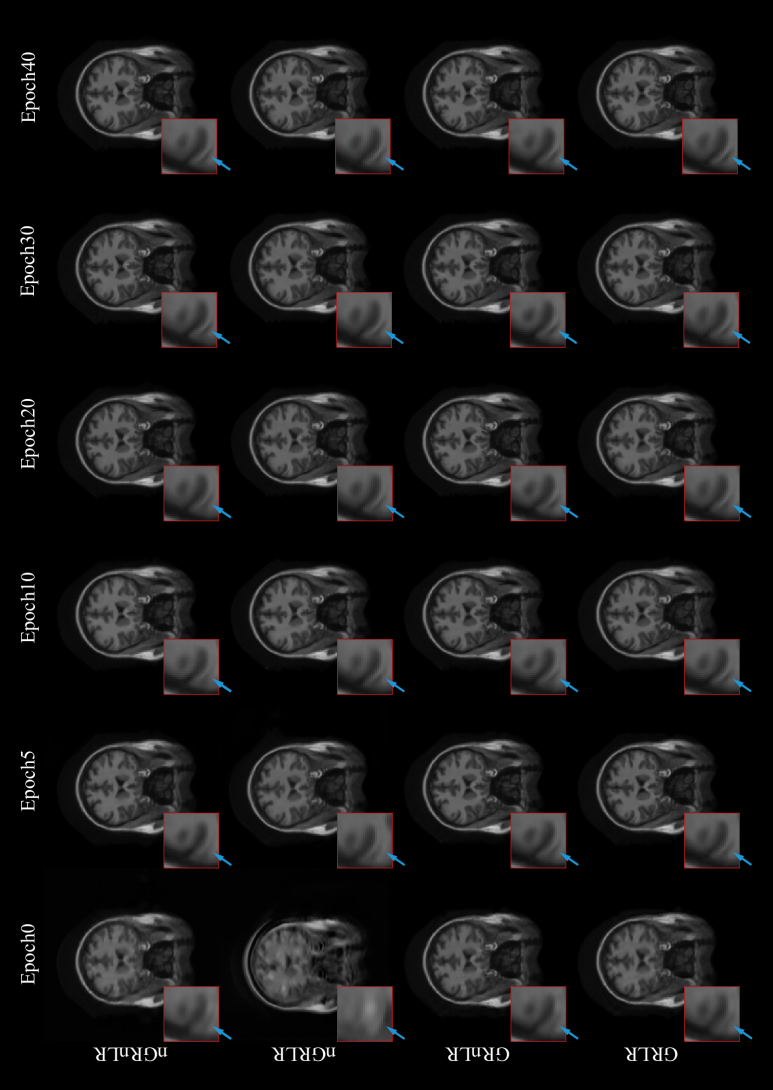

In this experiment, the effect of residual learning in the network was discussed. Our proposed model was tested on MICCAI 2013 grand challenge dataset, using Gaussian 1D 30% downsampling.

The experiment was divided into four groups: (1) GRLR (model with GR and LR), (2) GRnLR (model with GR without LR), (3) nGRLR (model with LR without GR), (4) nGRnLR (model without LR and GR). Early stopping strategy was turned off in this experiment to prolong the training process for a better and more distinguishable comparison for the training step.

Fig. 12 shows NMSE, SSIM, PSNR and generator loss (G Loss) of the four groups changing with the training process, and Fig. 13 shows testing examples with respect to different epoch weights.

Models with GR (GRLR, GRnLR) have faster convergence and better final results compared with those without GR (nGRLR, nGRnLR). If the model applies GR, then using LR has little further impact effect on the results. For non-GR models, nGRLR converges significantly slower than nGRnLR but final results are superior. Therefore, we chose GRLR as the generator for subsequent study.

Figure 13: Testing examples of the ablation studies with residual learning. GRLR: model with GR and LR; GRnLR: model with GR without LR; nGRLR: model with LR without GR; nGRnLR: model without LR and GR.

4 Discussion